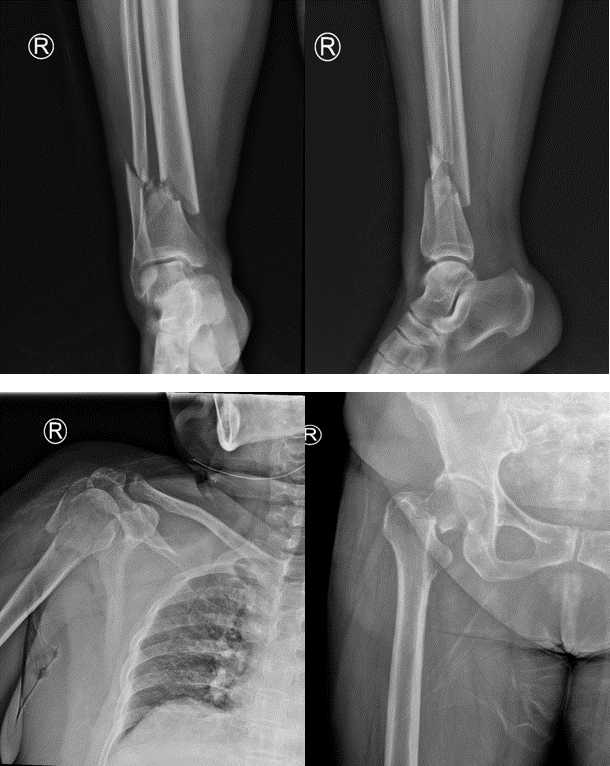

老家安徽的陈女士在苏州工业园区已经生活了很多年,一年前不幸遭遇车祸,当时短暂昏迷,全身疼痛无法活动,右侧耳还伴有出血。送至我院急诊后,诊断为:脑挫裂伤、肺挫伤、颅骨骨折、右侧上下肢骨折、右侧多根肋骨骨折,遂将患者收住重症监护室进行抢救治疗。

骨折X线

病情稍有稳定后,其它治疗迫在眉睫,如不能抓紧手术,严重的并发症将使患者再次陷入危险之中。骨科何罕亮副主任医师综合考虑患者情况,决定实施分期手术。第一次先行肱骨骨折切开复位内固定术 +胫腓骨骨折切开复位内固定术,第二次视患者情况择期行全髋关节置换术。

第一次手术的关键在于速度要快!这一次手术一共需要处理两个部位、三处骨折,为了尽量减少对患者的影响,手术要求在短时间内完成。何罕亮医师团队术前仔细研究病情,术中精细操作,全部手术在3小时内顺利完成,手术中出血仅130ml,术后复查X线显示骨折对位对线良好。

第一次术后复查X线